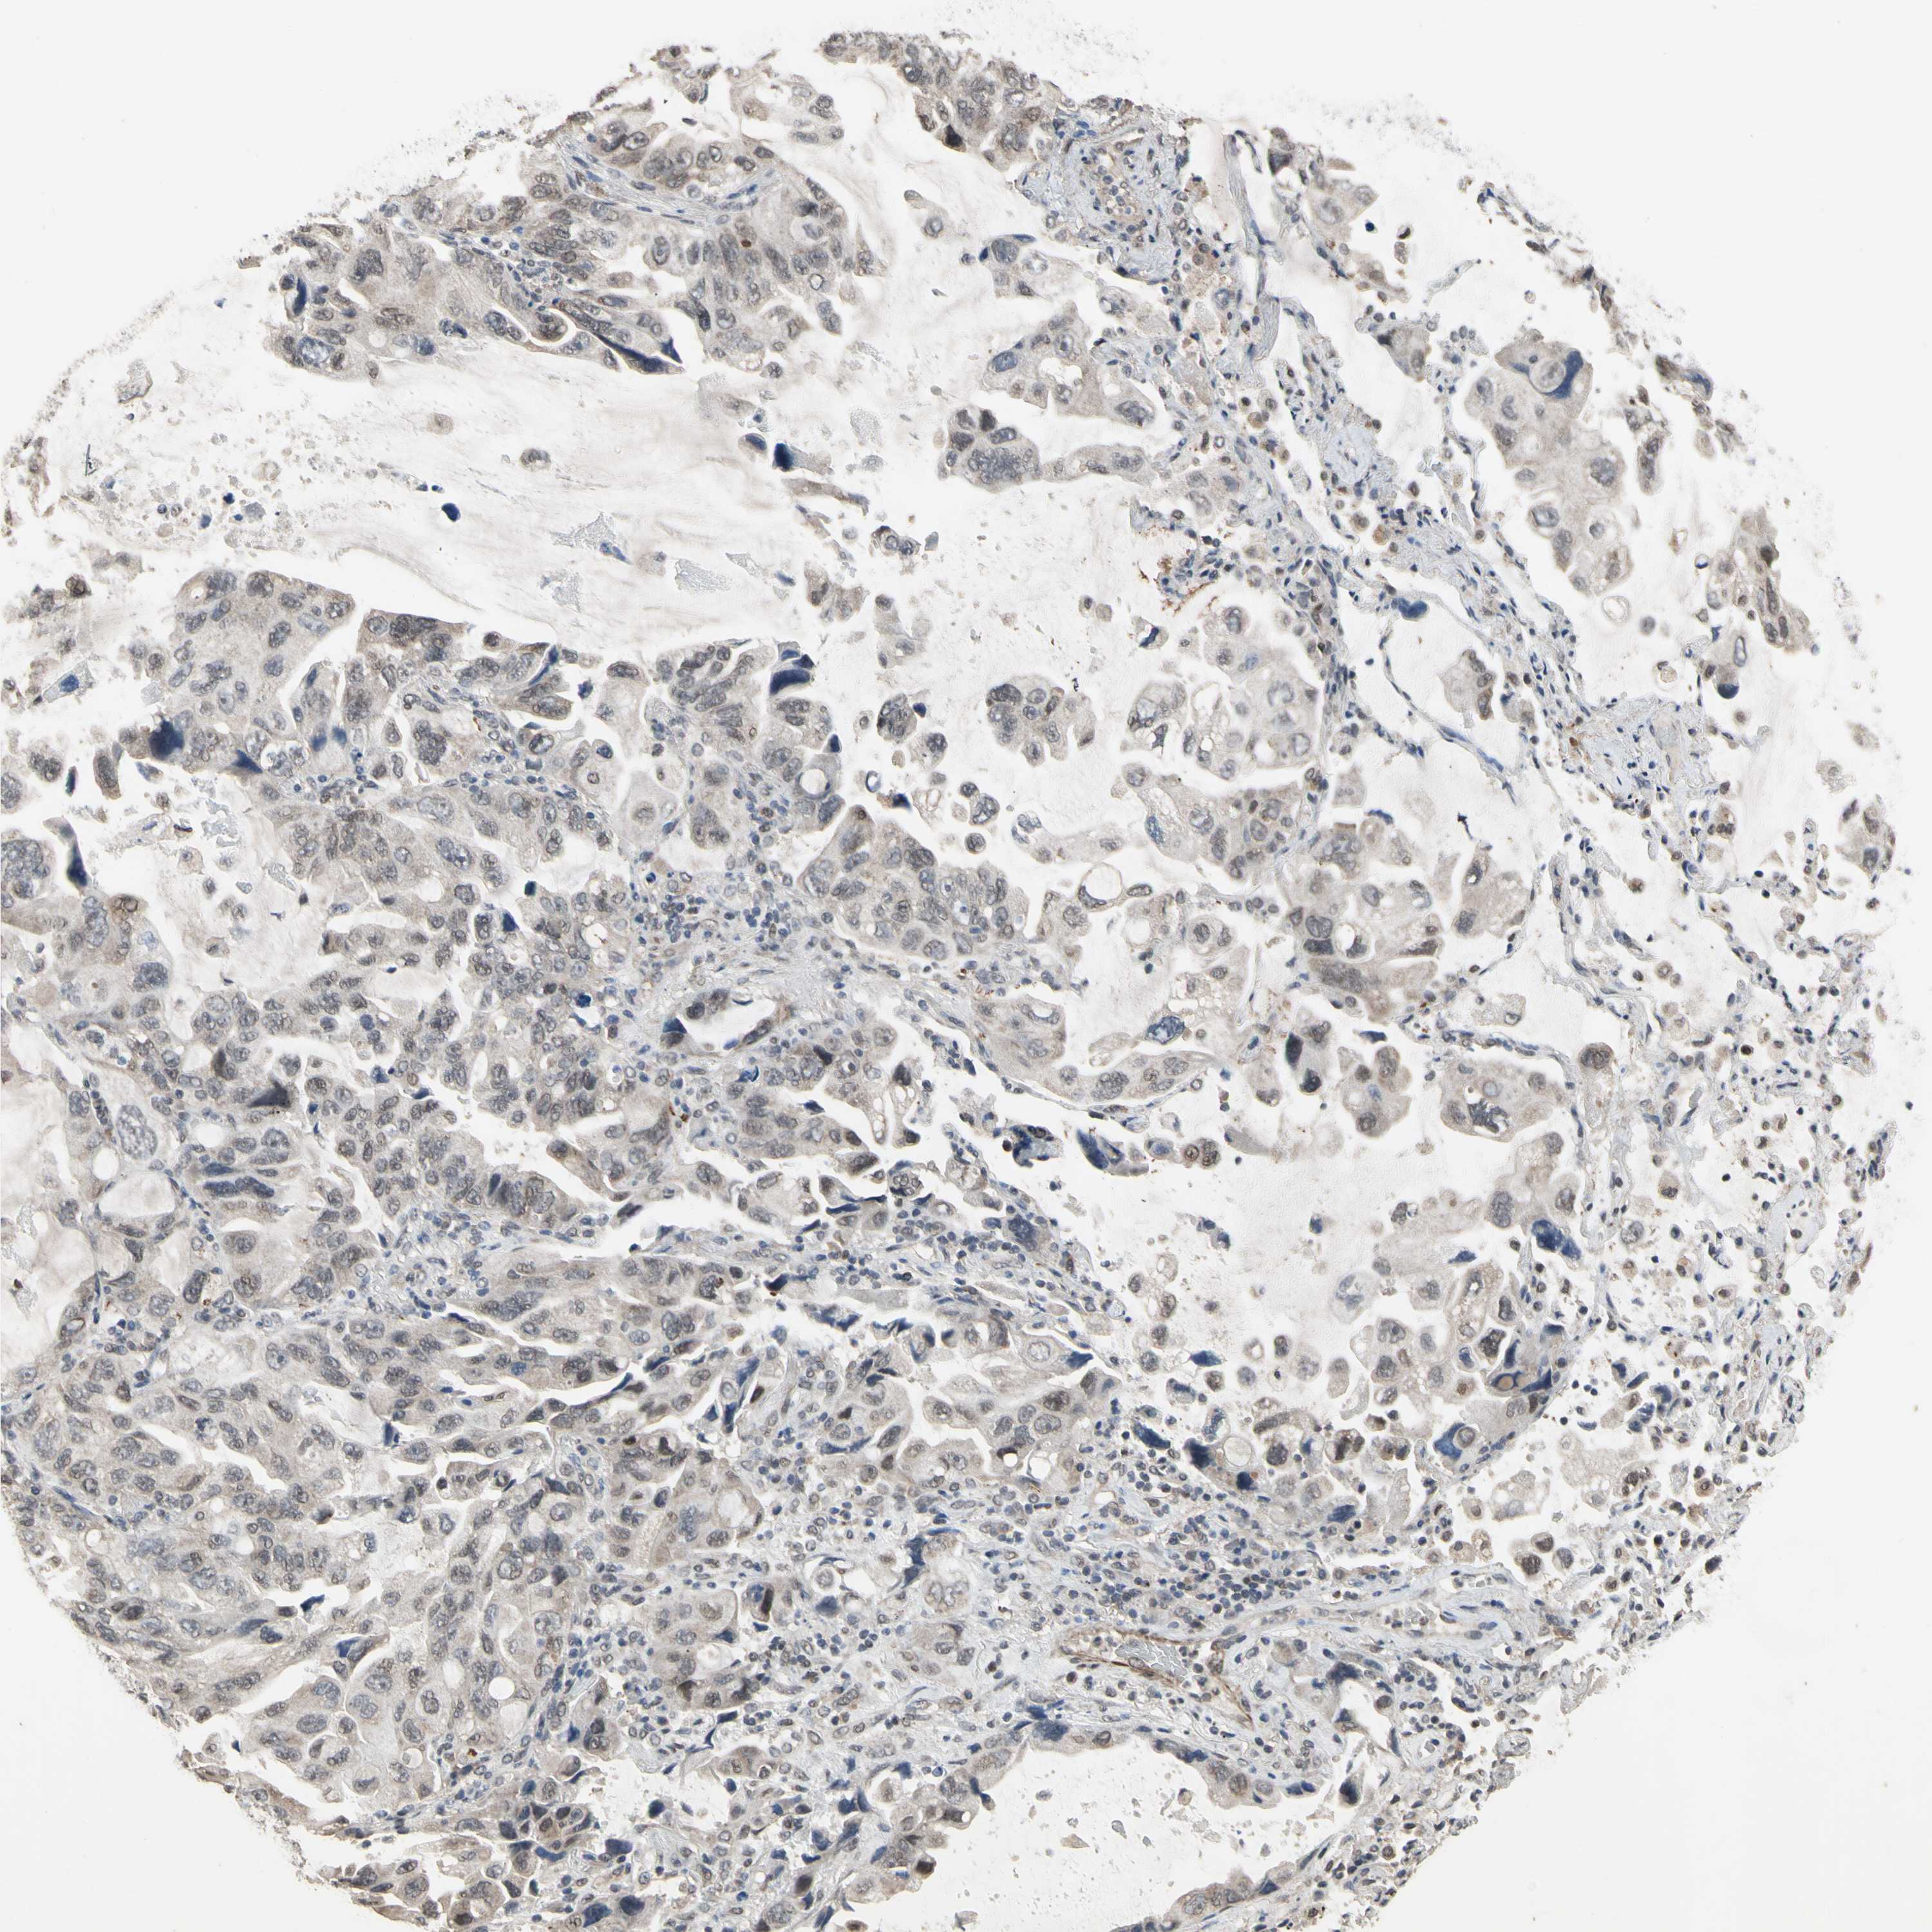

LUNG SQUAMOUS CELL CARCINOMA (TCGA) - Interactive survival scatter ploti

The Survival Scatter plot shows the clinical status (i.e. dead or alive) for all individuals in the patient cohort, based on the same data that underlies the corresponding Kaplan-Meier plots. Patients that are alive at last time for follow-up are shown in blue and patients who have died during the study are shown in red.

The x-axis shows the expression levels (FPKM) of the investigated gene in the tumor tissue at the time of diagnosis. The y-axis shows the follow-up time after diagnosis (years). Both axes are complimented with kernel density curves demonstrating the data density over the axes. The top density plot shows the expression levels (FPKM) distribution among dead (red) and alive patients (blue). The right density plot shows the data density of the survived years of dead patients with high and low expression levels respectively, stratified using the cutoff indicated by the vertical dashed line through the Survival Scatter plot. This cutoff is automatically defined based on the FPKM cutoff that minimizes the p-score. The cutoff can be changed by dragging the vertical line or by entering a cutoff value in the square labeled "Current cut-off".

Under the Survival Scatter plot the p-score landscape (black curve; left axis) is shown together with dead median separation (red curve; right axis). Dead median separation is the difference in median mRNA expression between patients who have died with high and low expression, respectively. It is calculated as follows: median FPKM expression of dead patients with high expression - median FPKM expression of dead patients with low expression. This is intended to aid the user in visually exploring custom cutoffs and the associated p-scores and dead median separation.

Individual patient data is displayed and can be filtered by clicking on one or more of the category buttons on the top of the page. Categories describing expression level and patient information include: high, low, alive, dead, female, male and tumor stages. The scale of the x-axis can be toggled between linear and log-scale by clicking on the "x log" button. Mouse-over function shows TCGA ID, patient information and mRNA expression (FPKM) for each patient.

& Survival analysisi

Kaplan-Meier plots summarize results from analysis of correlation between mRNA expression level and patient survival. Patients were divided based on level of expression into one of the two groups "low" (under cut off) or "high" (over cut off). X-axis shows time for survival (years) and y-axis shows the probability of survival, where 1.0 corresponds to 100 percent.

ZNF174 is not prognostic in Lung Squamous Cell Carcinoma (TCGA)

Best expression cut offi

Based on the FPKM value of each gene, patients were classified into two groups and association between prognosis (survival) and gene expression (FPKM) was examined. The best expression cut-off refers the FPKM value that yields maximal difference with regard to survival between the two groups at the lowest log-rank P-value. Best expression cut-off was selected based on survival analysis .

When clicking on this number, the vertical dashed line indicating cut-off, the interactive survival plot, and the Kaplan-Meier curve will be adjusted to show results based on the best expression cut-off.

: 6.46

P scorei

Log-rank P value for Kaplan-Meier plot showing results from analysis of correlation between mRNA expression level and patient survival.

N/A

TCGA RNA samplesi

RNA-seq data is reported as average FPKM (number Fragments Per Kilobase of exon per Million reads), generated by the The Cancer Genome Atlas (TCGA) .

Normal distribution across the dataset is visualized with box plots, shown as median and 25th and 75th percentiles. Points are displayed as outliers if they are above or below 1.5 times the interquartile range. FPKM values of the individual samples are presented next to the box plot.

Average pTPM 9.0

Number of samples 489